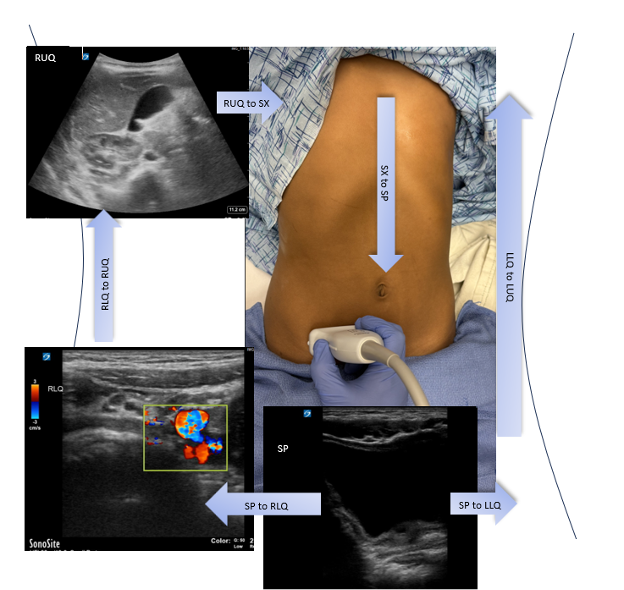

Patient is positioned supine and the abdomen is scanned systematically in both transverse and longitudinal planes. Employing the lawnmower technique aids to ensure all areas of the abdomen are scanned (Fig. 3). Gentle graded compression is applied to displace bowel gas.

(Figure 4)

Figure 4: Lawnmower Method

Identify bladder in Suprapubic (SP) View, start moving the probe laterally to the Right Lower Quadrant (RLQ) and identify iliac vessels. Keep moving the probe laterally until you identify the iliac crest. The ileocecum is cephalud to the iliac crest. Then move cephalically toward the Right Upper Quadrant (RUQ). Rotate probe with probe marker facing up and advance probe medially to the Subxiphoid area (SP). Rotate probe again with probe marker facing right and advance probe caudally though the center of the abdomen, stopping after you obtain the SP view again. Then progress to capture the Left Lower Quadrant (LLQ) by moving laterally, and finally by obtaining the Left Upper Quadrant (LUQ) by advancing probe cephalically.